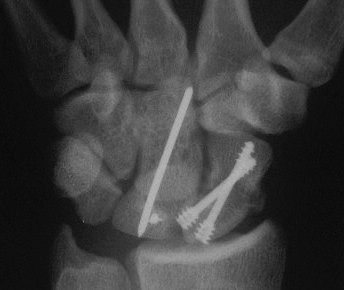

Case 8. Transscaphoid perilunate fracture dislocation...

Click for larger image

Two screws put in dorsally, LT ligament reinforced with a strip of extensor retinaculum left attached to the triquetrium and anchored into the lunate; temporary capitolunate pin.